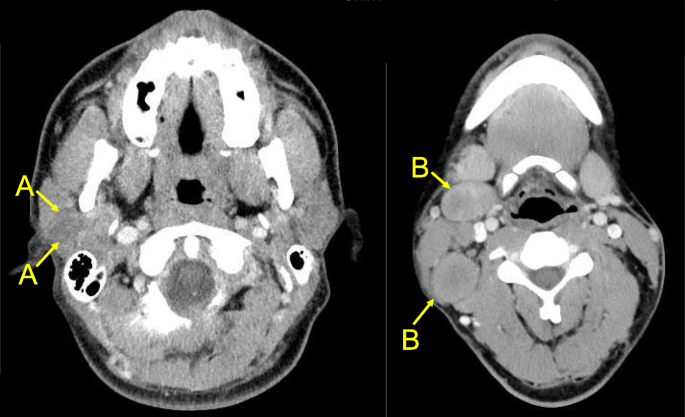

- High-grade MEC are characterized by:

- The invasion of adjacent structures

- Atypical mitoses

- Necrosis

- Perineural invasion

- Lymph node metastasis:

- 40% to 50%

- Distant metastases